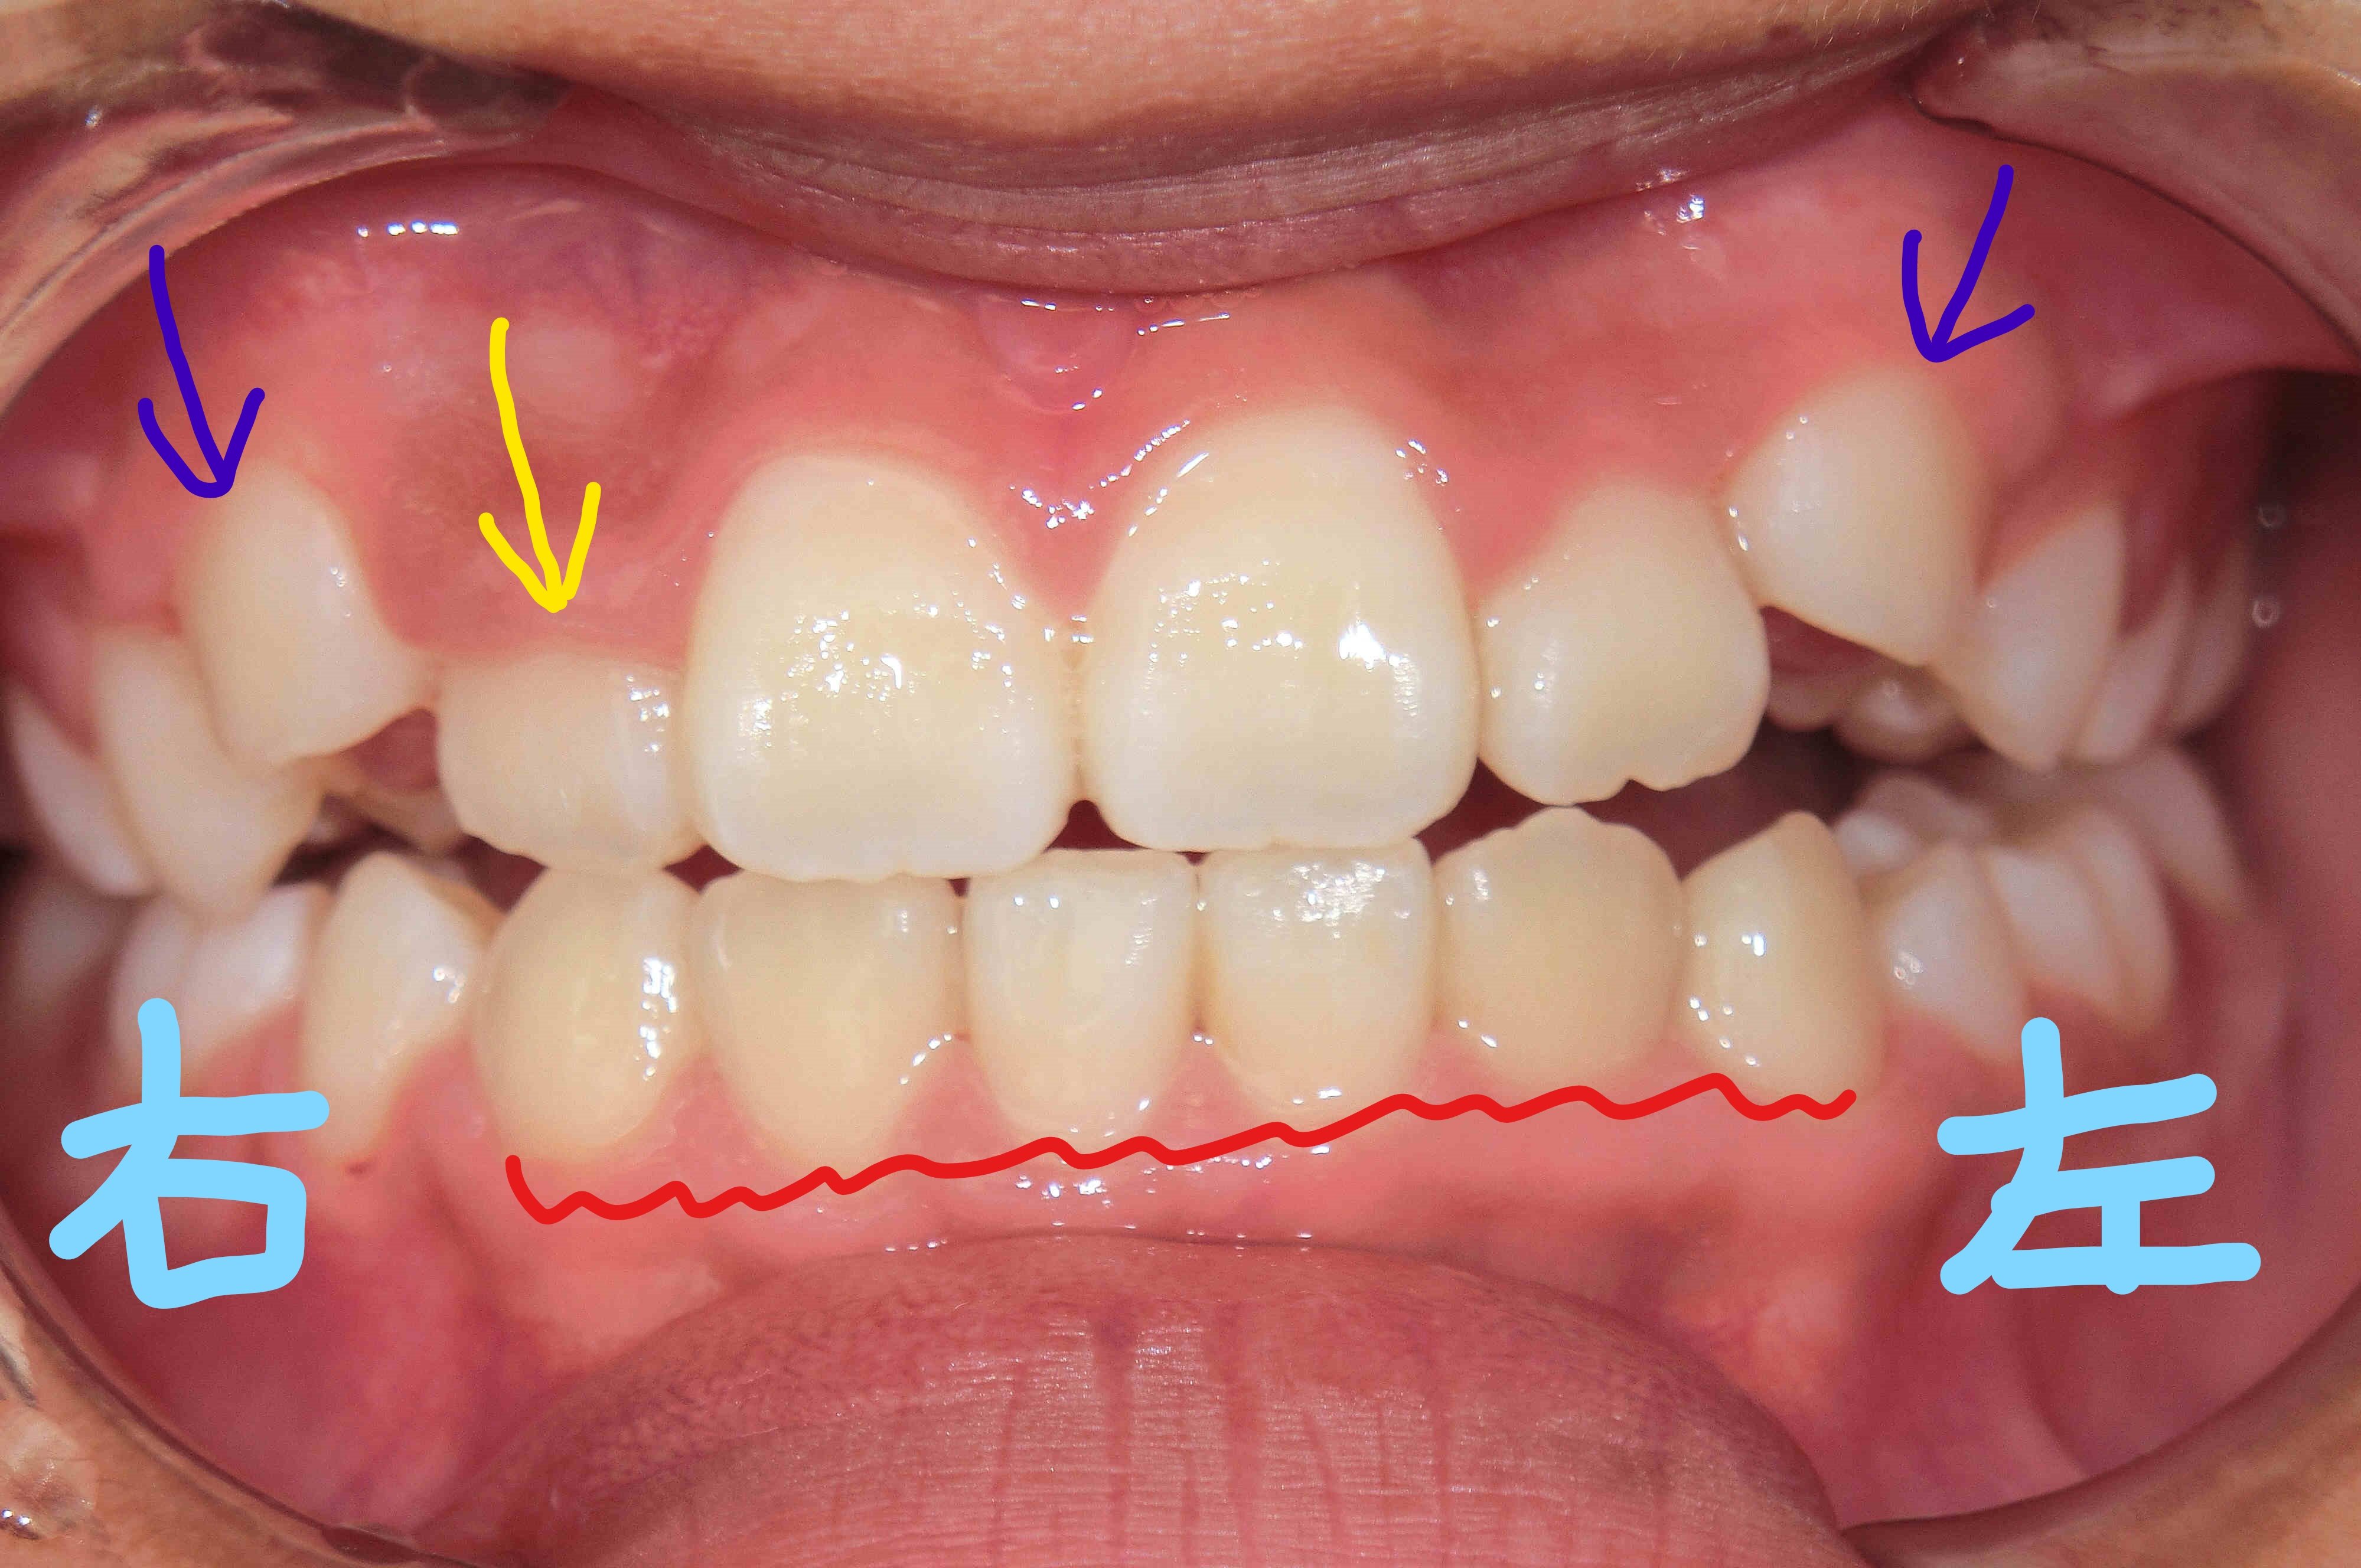

さらに、左上の写真は上顎を下から見たもので、右上の写真は下顎を上から見た写真です。前歯の整列が進む一方で、上顎の拡大がまだ十分ではないと判断しています。その理由は、上顎犬歯(紫色矢印の歯)が歯列の外側に萌出し、いわゆる「八重歯」になる可能性があるためです。

とはいえ、下顎の叢生が整い始めていることは、治療の進行として望ましい兆しといえるでしょう。一般的に、下顎の歯列調整は上顎よりも難しいとされており、この段階での改善は非常に前向きな変化と考えられます。